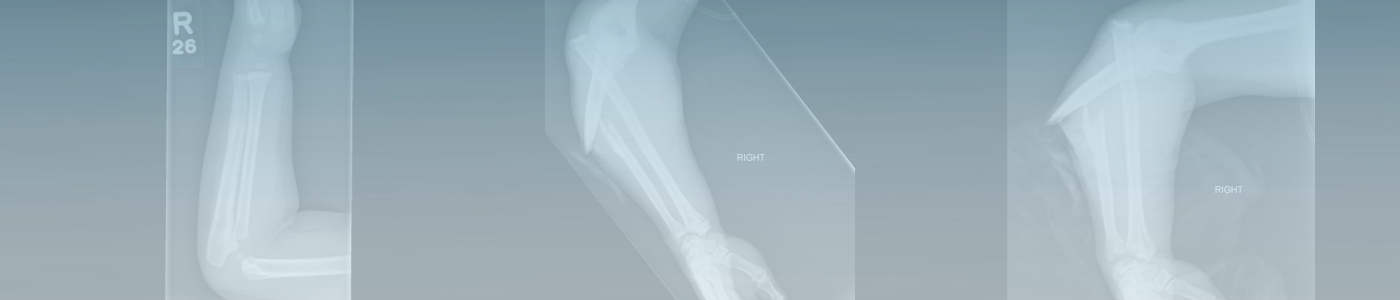

Join us for the upcoming Emergency Radiology — MSK Virtual Course. In this virtual course led by Manickam Kumaravel, MD, you’ll have the opportunity to study and interpret upper extremity trauma in an ER setting and develop a high level of expertise and confidence in emergent upper extremity trauma imaging.

• Review common and uncommon fractures of the upper extremities with emphasis on the “easily missed” fracture.

• Recognize common and significant injuries in trauma and their clinal significance.